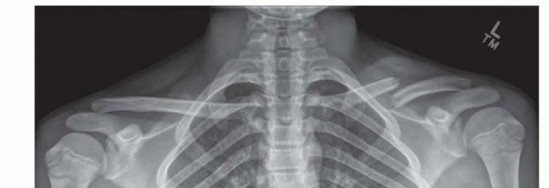

Chapter 20 Open Reduction and Internal Fixation of Clavicular Fractures J. Todd R. Lawrence R. Justin Mistovi…